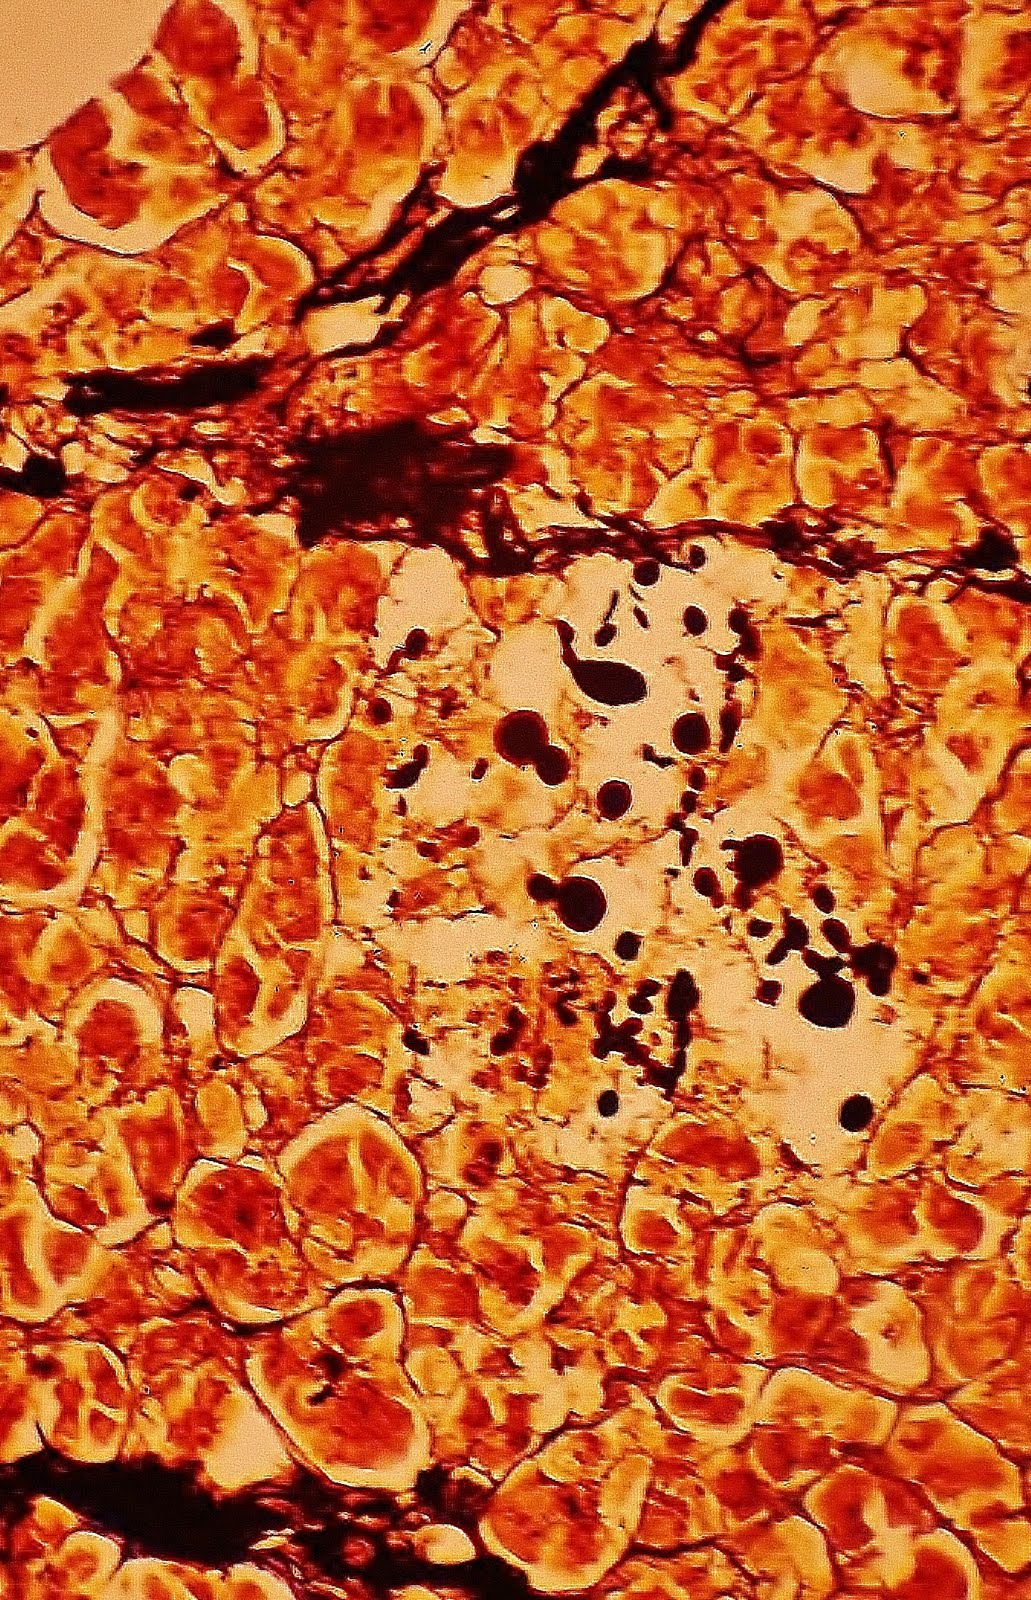

Entre los miocardiocitos, visualizados en corte tranversal, se localizan pequeños quistes (o seudoquistes), que contienen las levaduras. Algunas formas se encuentran en fase de gemación.

En la fotografía se puede apreciar que algunas blastoconidias de criptococo neoformans se encuentran rodeadas por el típico halo claro capsular, PAS negativo; en verde, los miocardiocitos.

Prof.Garfia.A